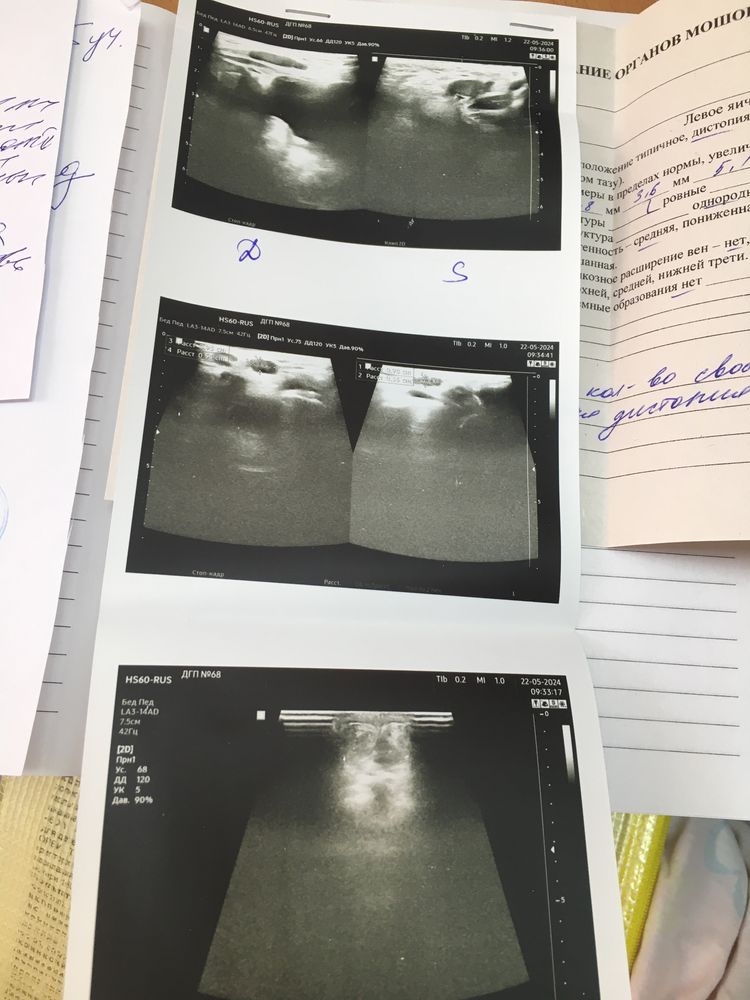

Здравствуйте! Сыну 1 год 2 месяца. У нас с рождения не опущены оба яичка в мошонку. До года с хирургом и с андрологом ждали, но ничего не произошло. Вопрос на контроле, сейчас уже записаны на операцию. Недавно нам делали узи, и меня немного напугало, врач отметила, что яички имеют очень малый размер, не соответствующий возрасту… Наш хирург никак это не прокомментировал, я хотела бы понять, насколько критично это уменьшение? Это гипоплазия? Или при крипторхизме так всегда и яички вырастут после операции? Фото с узи прилагаю

Здравствуйте. Поскольку крипторхизм двусторонний и есть признаки дефицита объема яичек, ДО операции необходимо выполнить ряд исследований и провести медикаментозную подготовку к операции. Только так можно достигнуть оптимальный долгосрочный результат